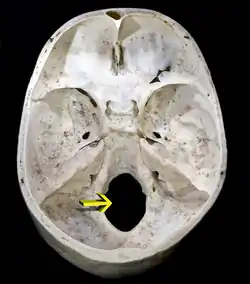

![]() Upper surface of base of the skull. The hole indicated by an arrow is the foramen magnum | |

The foramen magnum (Latin: great hole) is a large, oval-shaped opening in the occipital bone of the skull. It is one of the several oval or circular openings (foramina) in the base of the skull. The spinal cord, an extension of the medulla oblongata, passes through the foramen magnum as it exits the cranial cavity. Apart from the transmission of the medulla oblongata and its membranes, the foramen magnum transmits the vertebral arteries, the anterior and posterior spinal arteries, the tectorial membranes and alar ligaments. It also transmits the accessory nerve into the skull.

The foramen magnum is a large, oval-shaped opening (foramen) in the occipital bone of the skull.[2] It is present in humans, and in many other animals. Anteriorly, it is bounded by the basiocciput.[2] Posteriorly, it is bounded by the supraocciput.[2] Laterally, it is bounded by the occipital condyles.[2]

On the occipital bone, the foramen magnum presents two midline cephalometric landmarks. The opisthion is the midpoint on the posterior margin of the foramen magnum. The basion is located at the midpoint on the anterior margin of the foramen magnum.